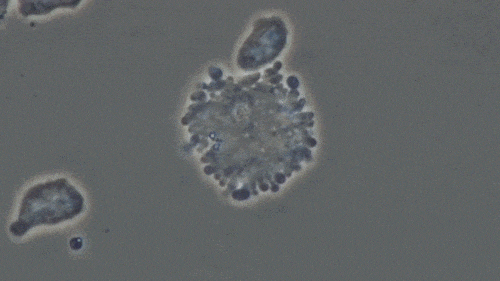

图片

NK细胞杀死癌细胞的过程